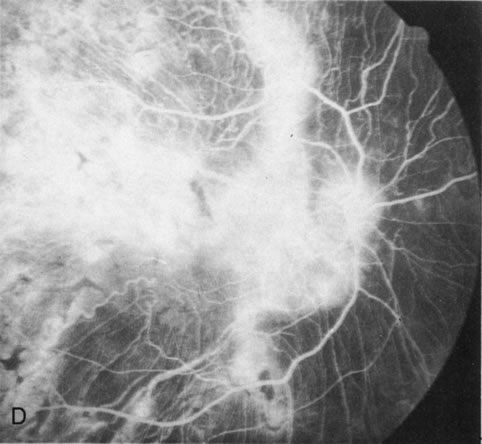

In retinitis pigmentosa (RP), the pigment abnormalities of atrophy, migration, and clumping are made apparent by transmitted hyperfluorescence and blocked hypofluorescence (Fig. 1A). Patients who have very minimal pigmentary alterations (pauci pigmentary RP) or no pigment abnormalities (RP sine pigmento) may show the abnormalities on fluorescien angiography (FA). It is uncommon to see choriocapillaris atrophy except in the late stages. This finding corresponds to the histopathology, which shows that the earliest abnormalities are in the photoreceptors and that the choroid is normal.1

Fig. 1. Retinitis pigmentosa. A. A typical area of bone spicule pigmentation. B. Diffuse dye leakage is apparent throughout the posterior pole. C. The early angiogram shows dilated and irregular retinal radial peripapillary capillaries and perifoveal retinal capillaries. D. Leakage from these vessels are evident in the late angiogram.

Dye leakage in RP may occur from the retinal vessels or at the level of the retinal pigment epithelium (Fig. 1B).2–4 The leakage may be seen in the macula and posterior pole, along the vascular arcades in the distribution of the radial peripapillary capillaries, and in the periphery (where an exudative vasculopathy resembling Coats' disease is suggested).

Of more clinical importance is the role of FA in the diagnosis and treatment of cystoid macular edema (CME) (Fig. 1C and D). Stereoscopic FA indicates that the leakage, which may be diffuse or have the typical petaloid stellate appearance of CME, can come from the perifoveal retinal capillaries, from the choroid through the RPE, or from a combination of both sources.4 With the recent suggestion that CME in RP may be successfully treated with acetazolamide,5, 6 FA is thus important to document the diagnosis of CME, establish the origin(s) of leakage, and follow patients during and after therapy.